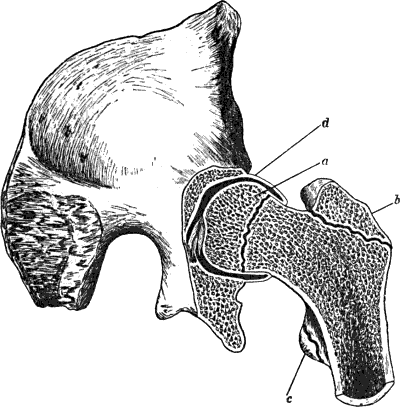

| 129. | Innominate Bone and Upper End of Femur from a case of Congenital Dislocation of Hip | 250 |